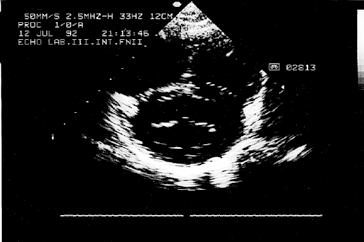

Kromě nakladatelství a výtvarníka se o definitivní podobu třetího dílu učebnice zasloužili mnozí odborníci. Za poskytnutí rtg snímků jsem již od vzniku 1. vydání 3. dílu učebnice vděčný Radiodiagnostické klinice 1. LF UK a paní doc. MUDr. Běle Drugové, DrSc., z radiodiagnostického oddělení Nemocnice Na Homolce. Za vynikající mikrofotografie z vývoje oka děkuji panu prof. MUDr. Františku Vrabcovi, DrSc., který mi je poskytl pro tuto knihu. Panu prof. MUDr. Oldřichu Eliškovi, DrSc., a paní doc. MUDr. Miloslavě Eliškové, CSc., děkuji za poskytnutí podkladů z jejich studií pro vytvoření obrazů mízního odtoku ze srdce. Panu doc. MUDr. Jaromíru Hradcovi, CSc., ze III. interní kliniky 1. LF UK děkuji za poskytnutí echokardiografických obrazů srdce. Upřímně děkuji též oběma spolupracovníkům, panu prof. MUDr. Rastislavu Drugovi, DrSc., a panu prof. MUDr. Miloši Grimovi, DrSc., za porozumění a sympatickou spolupráci na tomto vydání knihy. Studentům, učitelům anatomie i lékařům přeji, aby jim kniha sloužila jako užitečný průvodce a pomocník při studiu tohoto náročného oboru.